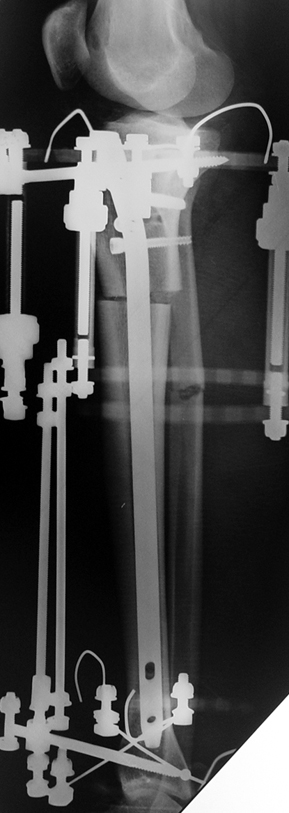

The patient lies is supine position at a traction table and legs are crossed with the uninvolved leg at the bottom. The medullary cavity is penetrated through piriform fossa using the standard method, and medulla is reamed 1.5 mm thicker than the nail to be used, over a guidewire. Proximal femur is reamed more, because the intramedullary nail is thicker proximally. The osteotomy site is planned at the X-Rays. It is important that at least 8 cm. of nail remains distal to the osteotomy site after the completion of the lengthening procedure. Percutaneous corticotomy is performed. The guide wire is advanced distally in order to measure the length of the nail. An intramedullary nail of apropriate length is placed. In the end, the nail is interlocked proximally, a suction drain is placed and the fist step of the operation is completed.

The application of the external fixator: Three Schanz screws are placed distally and three screws are placed proximally. At least 1 mm of distance shall remain between the screws and the nail.

In selected cases, we prefer to use a combination of a unilateral dynamic axial fixator and an interlocked intramedullary nail, in order to protect the length and alignment after the completion of the lengthening procedure. As a prerequisite for this technique, the narowest diameter of the medullary cavity shall be wider than 7 mm and the length of the nail segment distal to the osteotomy site shall be at least 8 cm. after the completion of the lengthening procedure.The intramedullary nail neutralizes shear and bending forces on femur during lengthening, shortens external fixation time, and protects newly formed bone against fractures. In our series, subtrochanteric osteotomy was performed in one case. No varus angulation occured despite the intramedullary nail.

Another complication of lengthening over nail in children is development of secondary coxa valga due to damaging of greater trochanter, which is close to the entry site of the nail. All cases but one in our series were skeletally mature. One case was 12 years old, and no coxa valga deformity was detected at last control. The case is still under control.